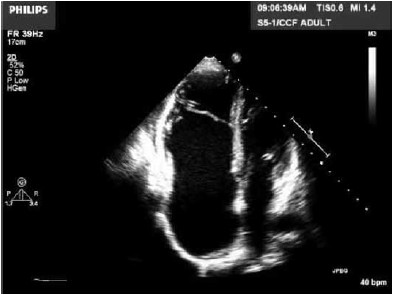

Mulher, 25 anos, apresenta intolerância aos esforços e palpitações. Realiza ecocardiograma apresentado na imagem a seguir.

(Arquivo pessoal; imagem usada com autorização)

Assinale a alternativa correta quanto à hipótese diagnóstica.